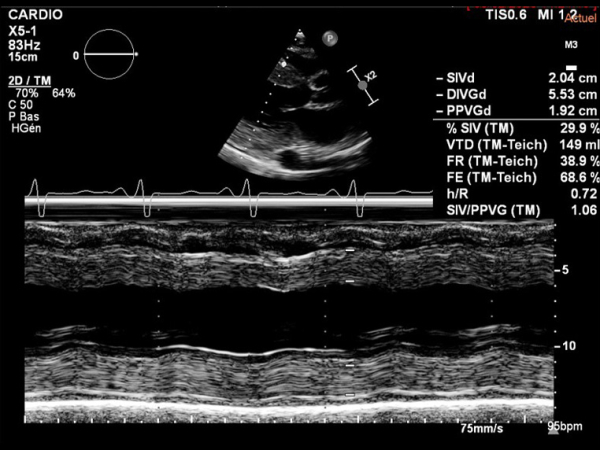

L'ETT montre :

- Dilatation modérée du VG. FEVG à 30%

- Cardiopathie hypertrophique sévère excentrique

Figure 1

Figure 2